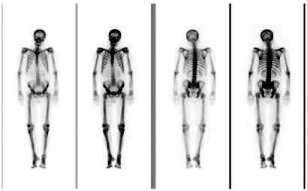

Scintigrafija kostiju - je radioizotopska dijagnostička

metoda koja pokazuje bilo kakva abnormalna područja kostiju. Radi se uvek

kada postoji klinička sumnja na koštane metastaze.

Scinografija osobe obolele od karcinoma pluća nemikroćelijskog tipa

– nema znakova koštane metastaze